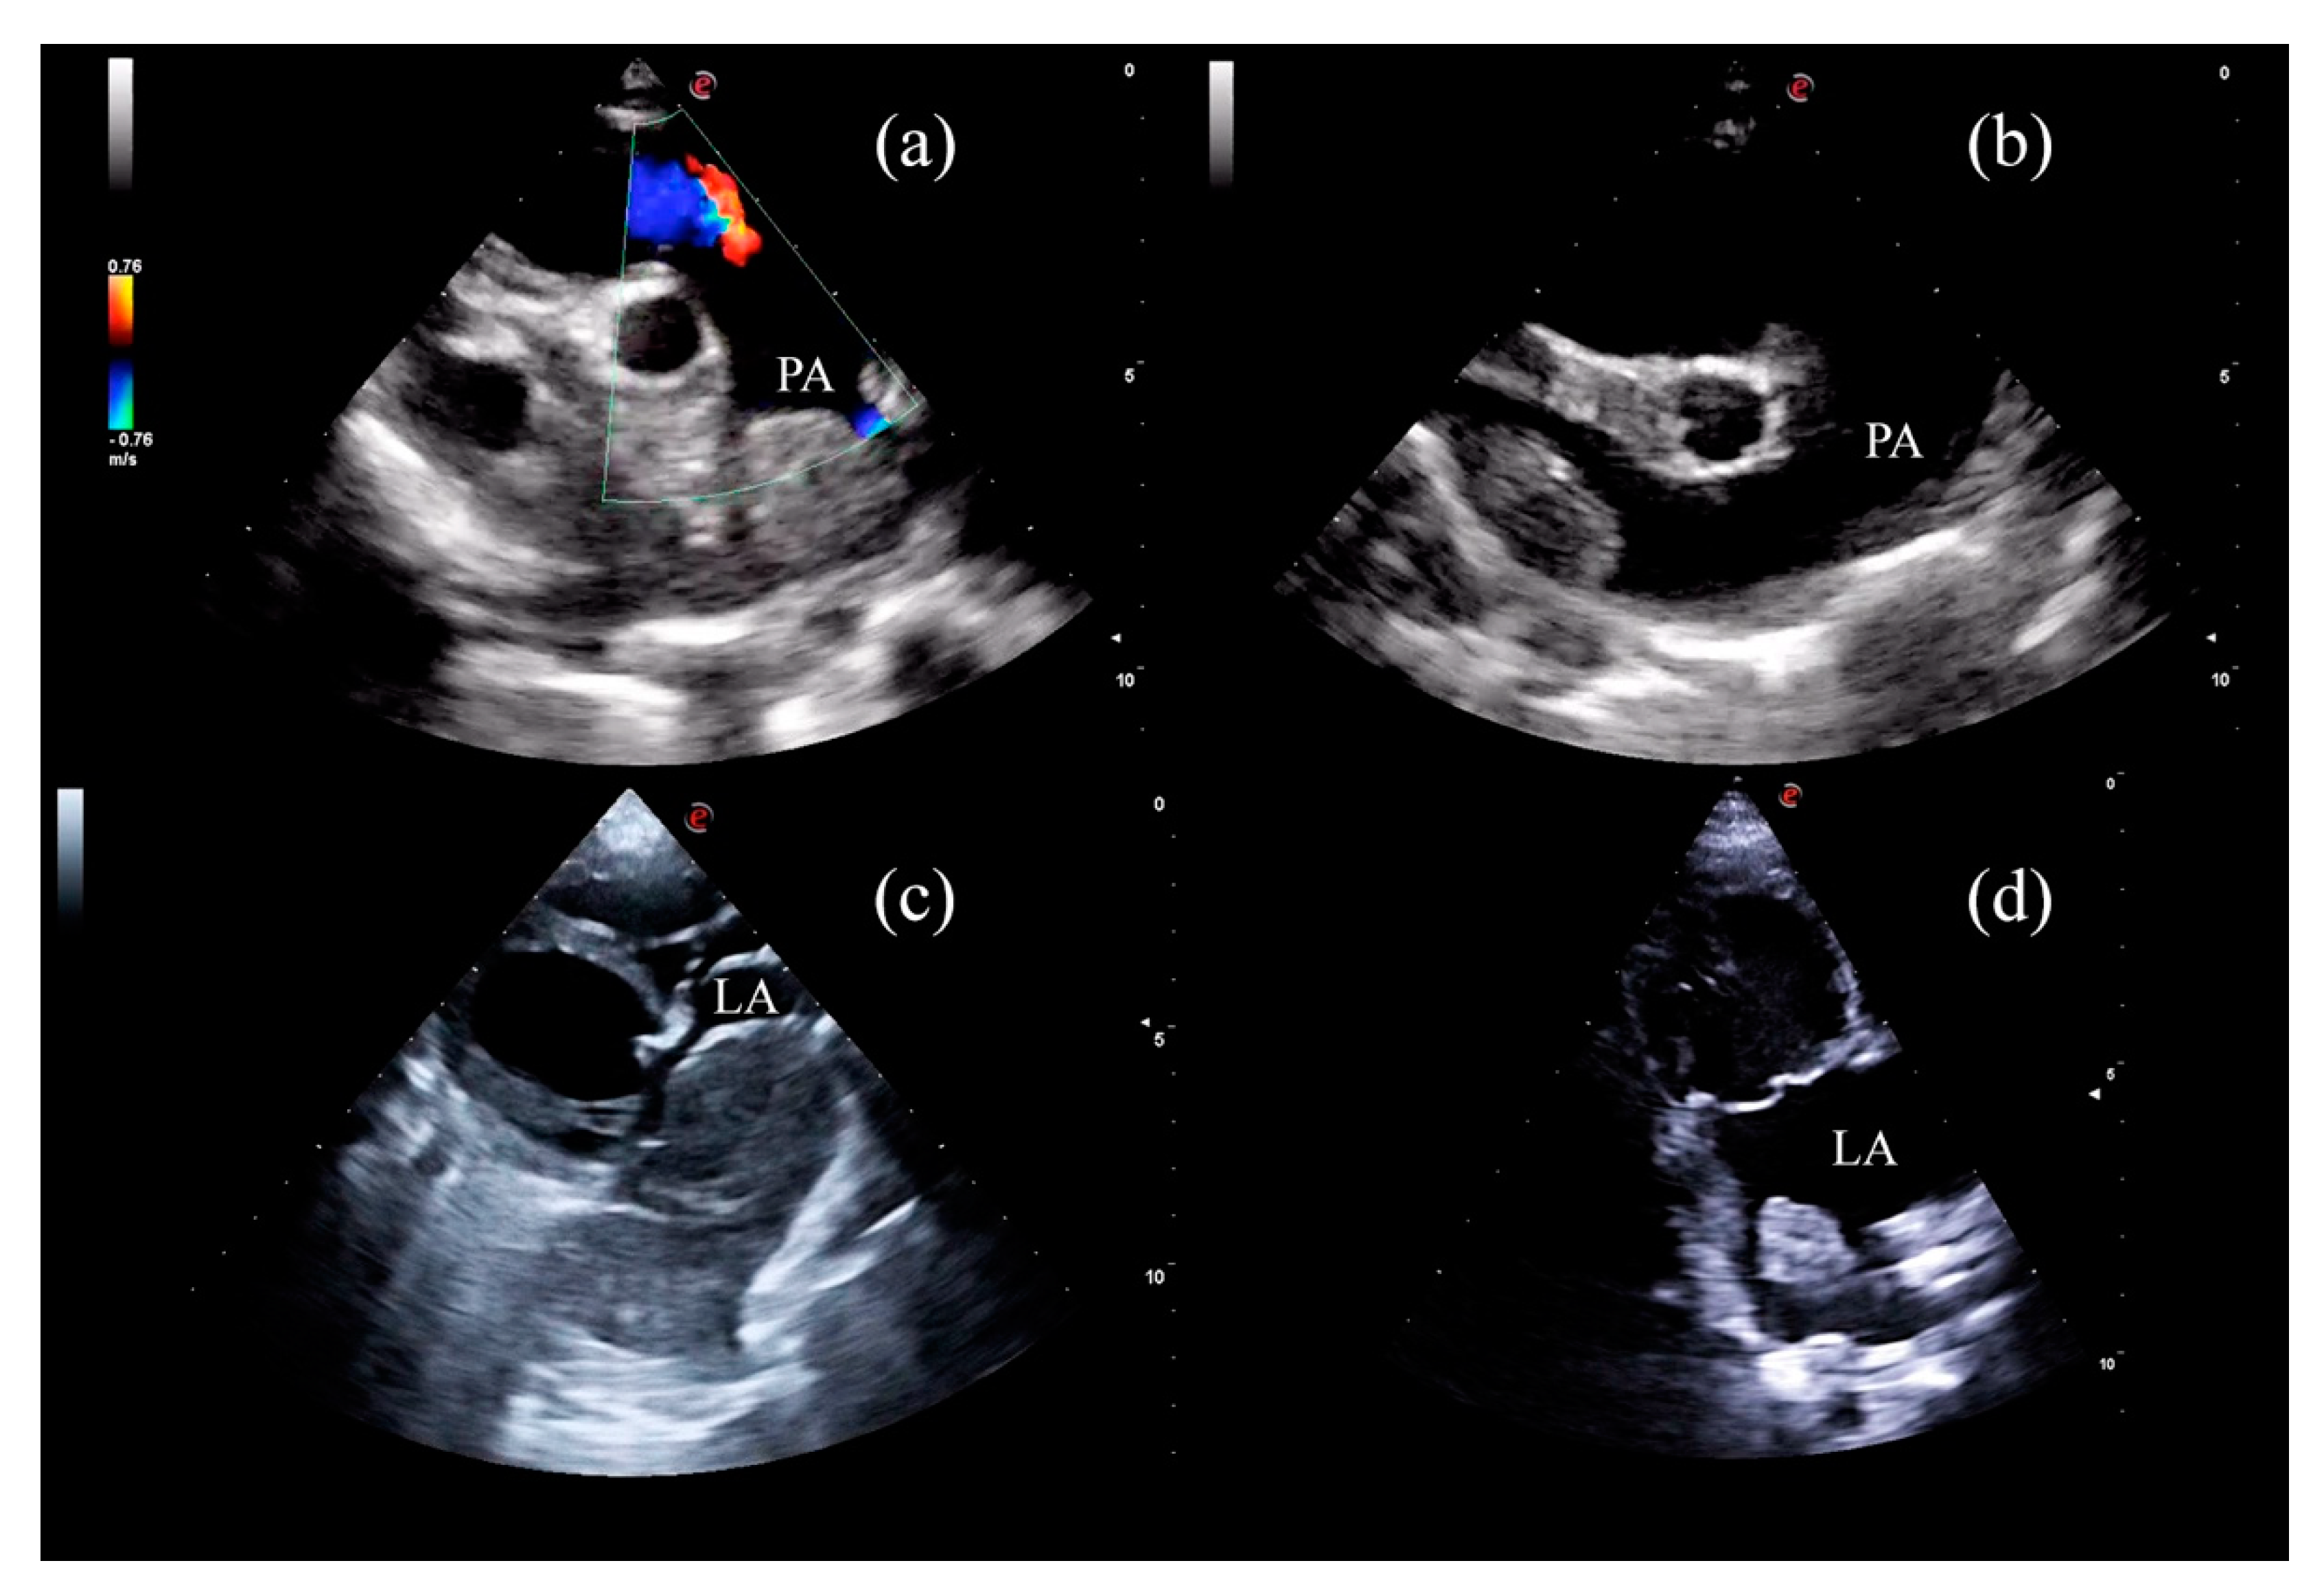

2. Materials and Methods

3. Results